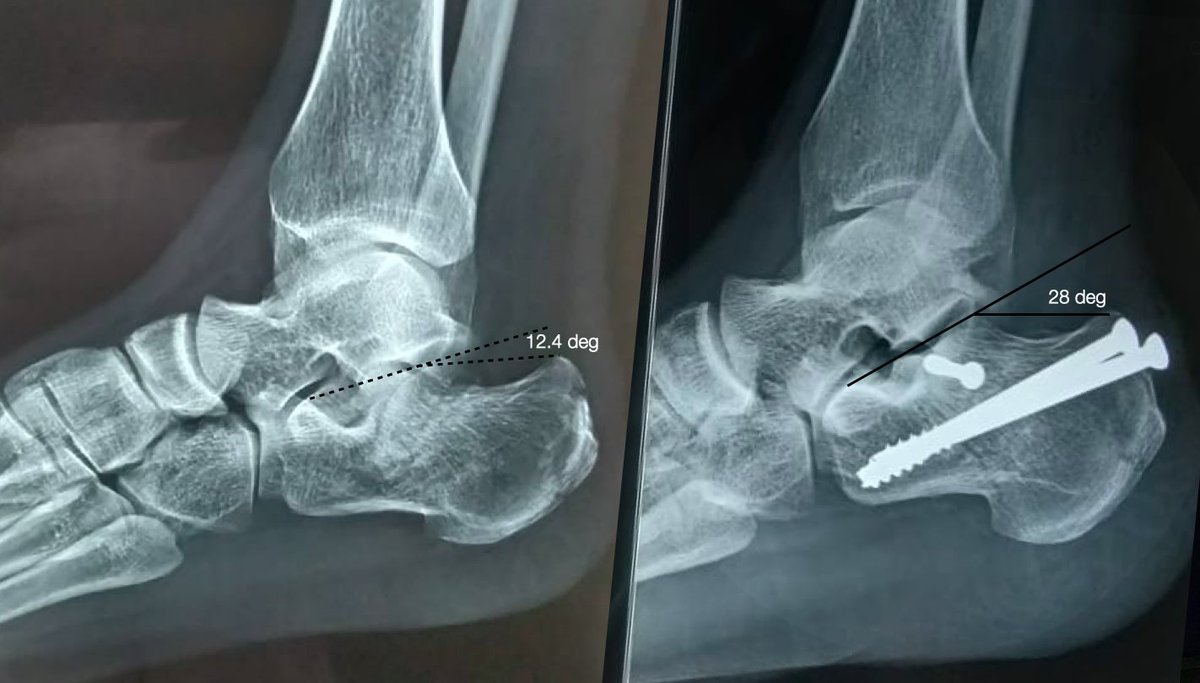

@karanshetty13 Posterior hinge has a part in this satisfaction .. 👌

Percutaneous fixation, two days after trauma. Attempted the technique described by Rodemund, Mattiassich et al (pubmed.ncbi.nlm.nih.gov/28101590/)

#orthotwitter #Orthopedics #MedTwitter